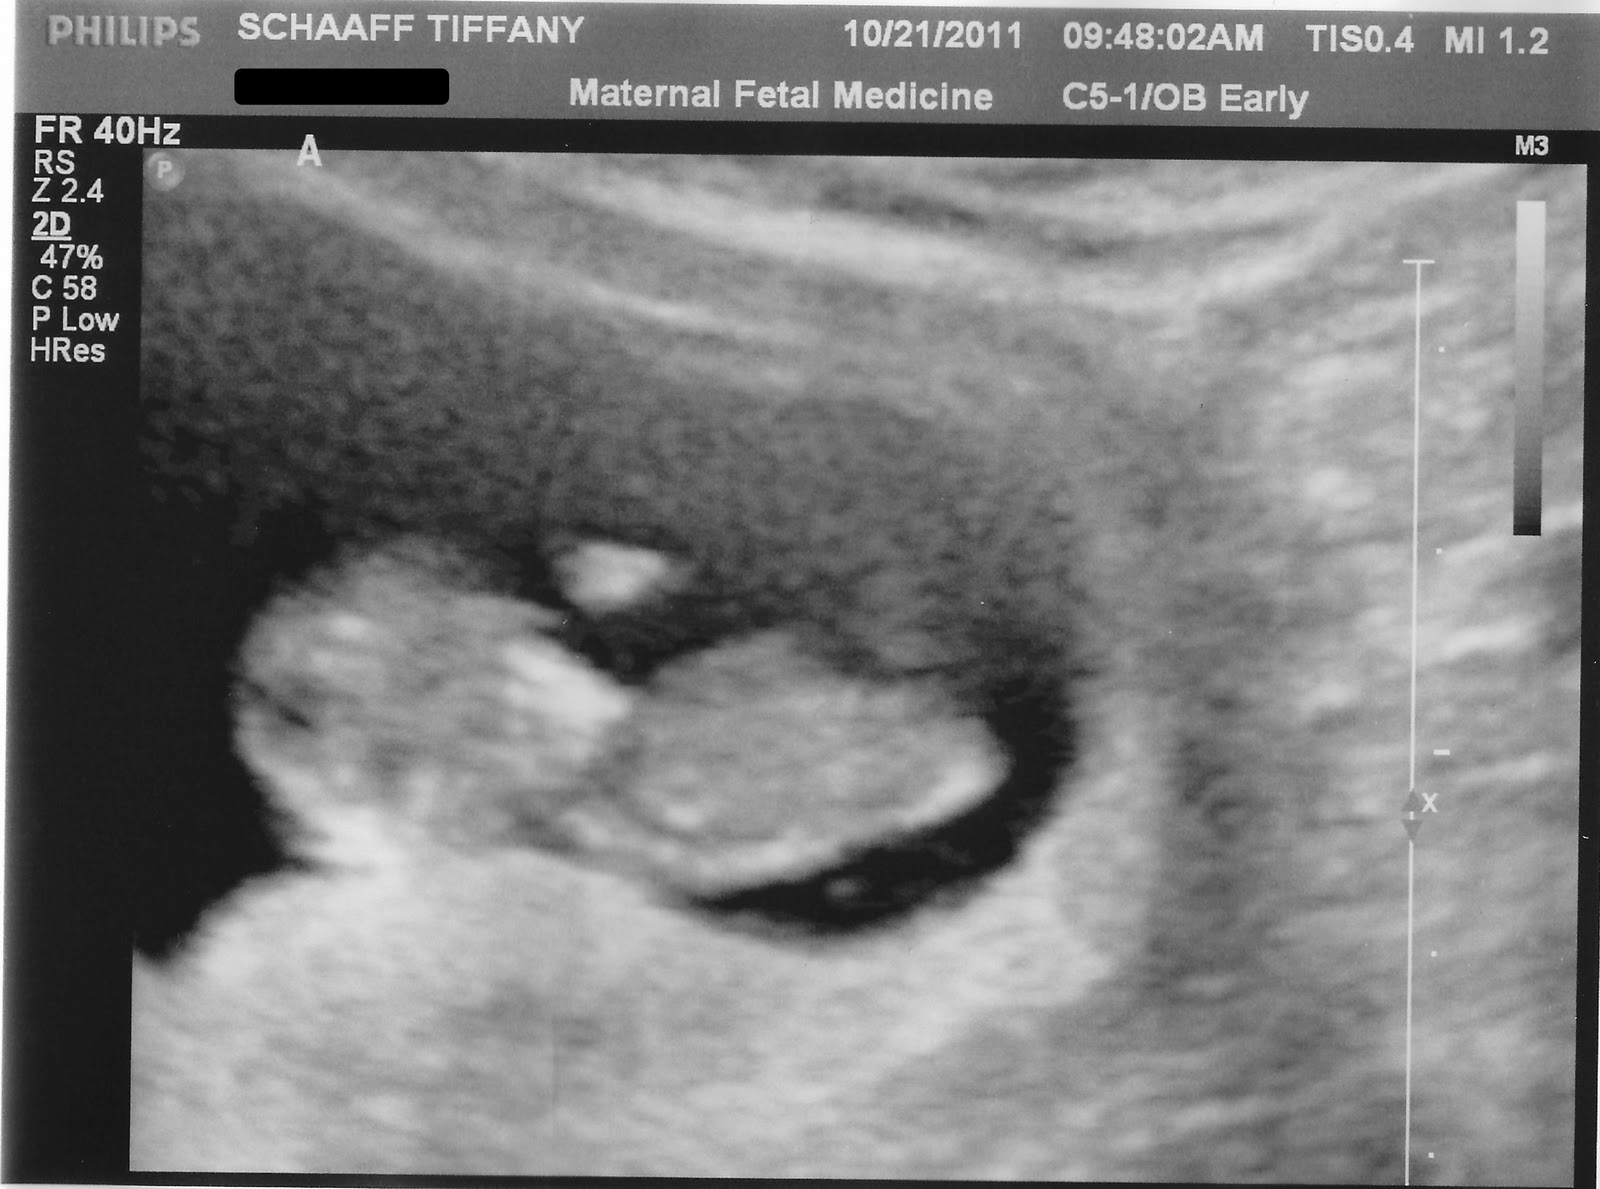

Daniel and I were so nervous and excited. Once we arrived at the dr's office we were taken directly to the ultrasound room. After having me give a urine specimen and checking my blood pressure and weight, finally the ultrasound tech came into the room. As she started the ultrasound my eyes caught something. There appeared to be 2 sacs. She hadn't said a peep, so I wondered if perhaps the other was not a sac. Maybe it was some medical not great thing, like a cyst. Then as she took a closer look the sentence "Ught Ohhhh." drops from her mouth. I knew as soon as I heard it that those 2 sacs were 2 babies!!!! Poor Daniel. His mind automatically went the other direction. He asked "What's wrong!?" and "Is our baby ok?!" The tech respondes with "You're having twins." Daniel totally thought she was joking. He wouldn't believe her. I told him she was truthful and that I saw it before she said anything. He asked again "Are you serious?" She replied with, "Better you than me." As he realized she was telling the truth all he could do was sweat. We were in utter shock. Over joyed, nerve wracked shock! I left the dr's office laughing all the way out! It was all I could do! This was beyond our imagination.